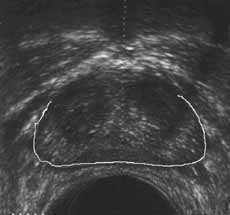

Рис. 13 и 14. (Слева) Фиброзно-мышечная строма предстательной железы. (Справа) Капсула предстательной железы.